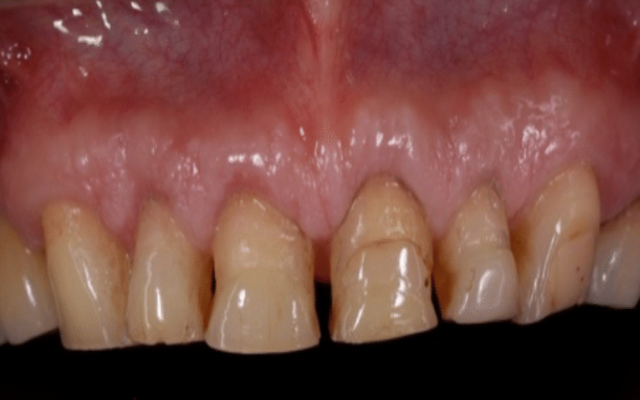

Crown lengthening can also be carried out for cosmetic reasons to expose more tooth structure to improve the appearance of the teeth or to reposition the gum tissues to an aesthetically acceptable position. This is a procedure that is often required where a patient has a “gummy smile” to reduce the amount of gum that is showing (Figure 9D, 9E and 9F).

Following crown lengthening, the gum has been repositioned to expose enough tooth structure for restoration with crowns.

The teeth have now been restored with long lasting crowns.